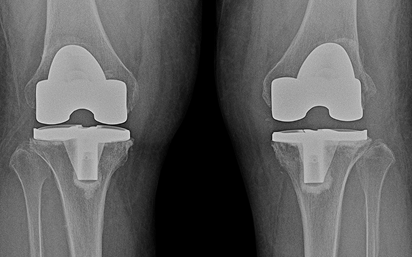

수술적 치료 : 인공관절 치환술

말기

인공관절 치환술

노화에 따른 퇴행성 관절염,외상 후 발생되는 외상성 관절염 등으로 손상이 심한 관절, 관절의 심한 변형과 극심한 통증을 해결하는 데 효과적으로 개인에게 맞게 인공 대체물을 삽입하는 수술 방법입니다.

무릎 관절 연골이 일부만 닮아 있을 경우, 선택적으로 인공관절 부분치환술을 시행 할 수 있습니다.적응증 (누가 하는가)

수술 전후 사례

-

수술 전

수술 후